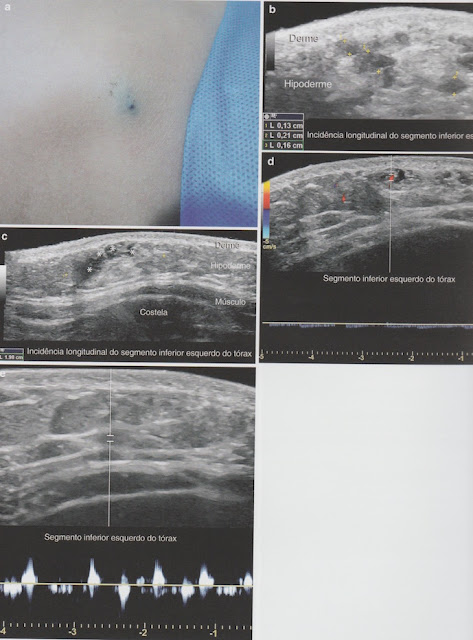

Malformação Vascular Venosa de Baixo Fluxo

Achados:

- Estruturas tubulares anecóicas, tortuosas ou áreas lacunares.

- Fluxo monofásico.